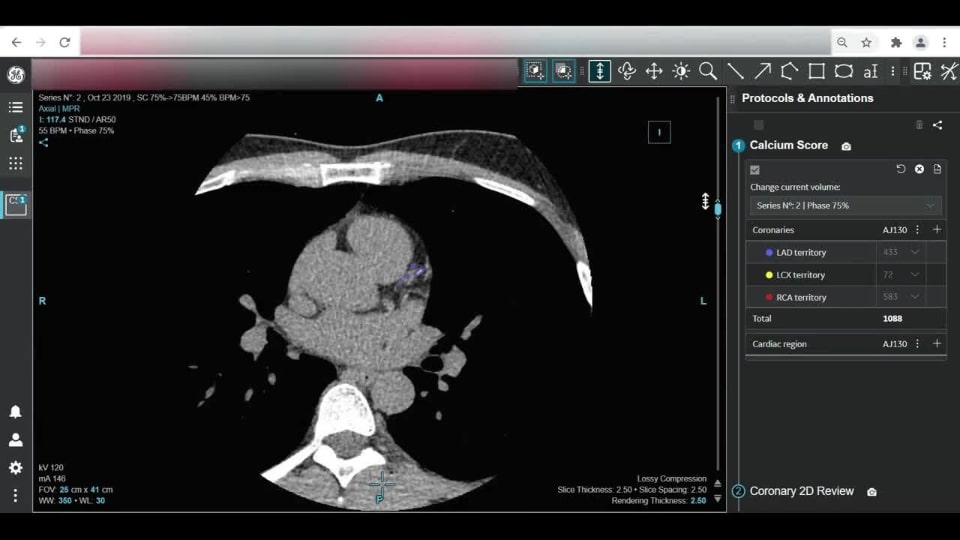

CardIQ Suite

CardIQ Suite provides an integrated workflow to seamlessly review calcium scoring and CCTA data. The fully automated calcium scoring algorithm identifies coronary calcium burden and location providing a total and per territory score within seconds of loading. Users can immediately move into the CCTA review, using cine capability for motion studies and double oblique tools for viewing the vasculature for a full review of coronary arteries and chambers.